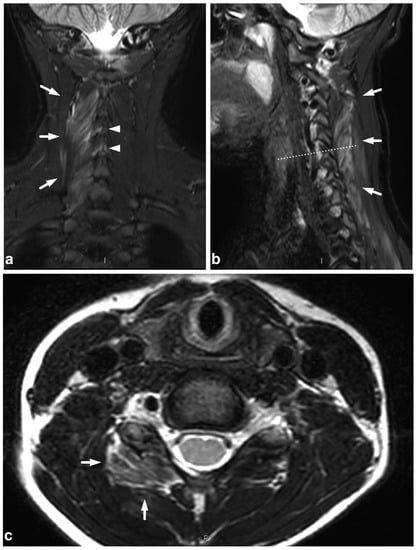

(a) Coronal STIR. (b) Sagittal STIR, off-midline right-sided image. (c) Axial T2-weighted, level C6 (dotted line in the image (b)). A 12-year-old male, cervical flexion injury in a trampoline accident. MRI demonstrates right-sided grade 1 muscle injury (white arrows) in the following muscles: rotatores, multifidus cervicis, interspinales, spinalis, and semispinalis. A minor edematous strain of the interspinous ligaments is seen at levels C5/6 and C6/7 (arrowheads).

5.3. Nerve Plexus Injuries

Treatment planning in nerve plexus injuries requires dedicated imaging [55,56]. However, in a trauma patient with neurological symptoms in the extremities, the emergency spinal MRI can be extended to immediately confirm or exclude a possible nerve plexus injury (Figure 13). If the dedicated neurography sequences are unavailable, routine fat-suppressed T2-weighted imaging provides good sensitivity in plexus injury detection [56].

Figure 13.

(a) Coronal STIR. (b) Sagittal T2-weighted. The dotted line in the image (a) represents the plane of the sagittal image (b) and vice versa. A 13-year-old male after a moped accident. MRI demonstrates a muscle injury and significant edema at the brachial plexus region (arrows). This emergency imaging was not definitive in assessing the extent of the injury. However, extending the cervical imaging to examine the plexus region tentatively helped to confirm the clinical suspicion of upper extremity paralysis being caused by a brachial plexus injury and not a central nervous system injury.